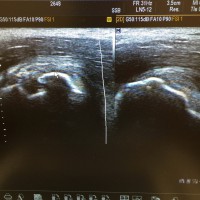

子どもに多い裂離骨折!症状が軽くてもご用心!!

こんにちは。 四ツ谷接骨院の安藤です。 まだまだ暑い日が続きますが、夏休みもあと1週間となりました。 皆さんは、どのような夏休みを過ごしましたか??? 院内で学生に聞くと、宿題の終わってない子が多いように …